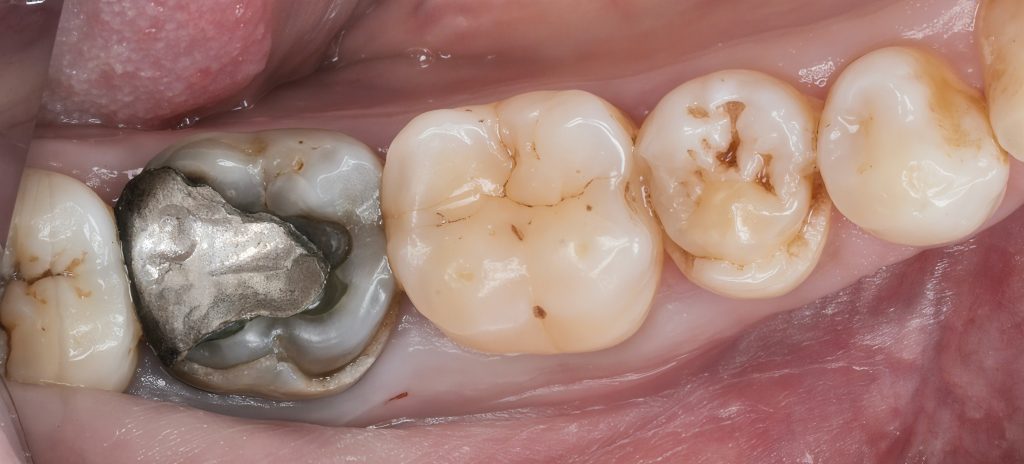

5. Immediate Post-Endo Build-Up (IDS + Reinforcement)

Before preparing the tooth for cuspal coverage, the internal structure was reinforced.

Immediate Dentin Sealing (IDS)

Freshly cut dentin was sealed immediately with a strong adhesive layer, improving bond strength and reducing polymerization stress.

Fiber-reinforced base

In areas of deep dentin loss, a fiber-reinforced composite layer (e.g., EverX / equivalent) was placed to reduce cusp flexure and strengthen the foundation.

Incremental composite build-up

Under magnification, composite was layered to reconstruct internal anatomy and core height with maximum control.

This stabilizes the tooth, prevents micro-movement, and ensures the final onlay sits on a strong, bonded platform.

6. Final Preparation for Composite Onlay

After the internal build-up cured and matured:

- Minimal cusp reduction was performed

- Internal line angles were rounded to reduce stress concentration

- Margins were kept supragingival whenever possible

- A conservative onlay design preserved maximum enamel

This preserves the tooth’s biomechanical integrity while allowing full cuspal protection.